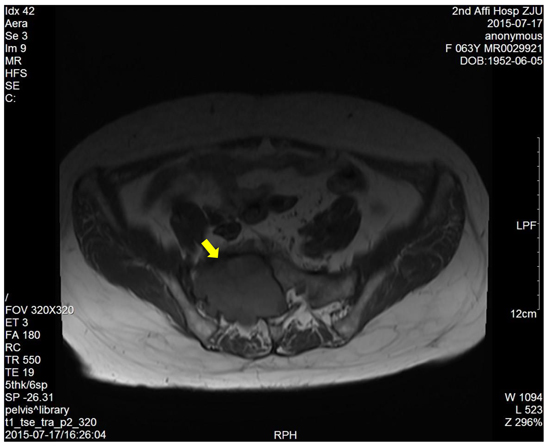

The dimension of the tumors was also shown in Table 1. Lumbosacral CT of our cases were characterized by expansive lesions located in high-sacra such as sacrum 1 and 2, mass appearance on the lateral caudal, well-circumscribed lesions with marginal sclerosis, and the overall benign presentation (Figure 1). In our study, the typical findings of sacral schwannomas in MRI were a well-circumscribed lesion with a heterogenous signal intensity on T2-weighted image. On T2-weighted image, low signal intensity was mixed on the basis of high signal intensity, which was found in our all cases (Figure 2). On T1-weighted image, slightly high signal intensity was mixed on the basis of low signal intensity, which was shown in two cases (Figure 3). Low signal on T1-weighted image was shown in eight patients (Figure 4). T1-weighted images of all cases are characterized by heterogenous enhancement (Figure 5). Average blood loss during surgery was 980ml (ranging between 100 and 2,000ml). Seven patients had only posterior approach as their tumors were limited to the sacrum; two patients went through both anterior and posterior interventions as their tumors extended to the anterior and posterior bone limits of the sacrum; one had just anterior intervention because the tumor was localized to the presacral region. All patients underwent an intralesional resection (piecemeal subtotal excision or shaving) to identify and preserve sacral nerve roots as much as possible. All patients were performed histological examinations after surgery to confirm the diagnosis of sacral schwannomas. Two patients had postoperative bowel and bladder dysfunction after surgery. But they gradually recovered after four months and three weeks, respectively. One patient had cerebrospinal fluid leakage and secondary intracranial infection. This patient finally recovered after several lumbar drainage and anti-infection treatment. All patients were ambulatory postoperatively.

Figure 4: T1-weighted image showed a right sacral mass with low signal intensity.